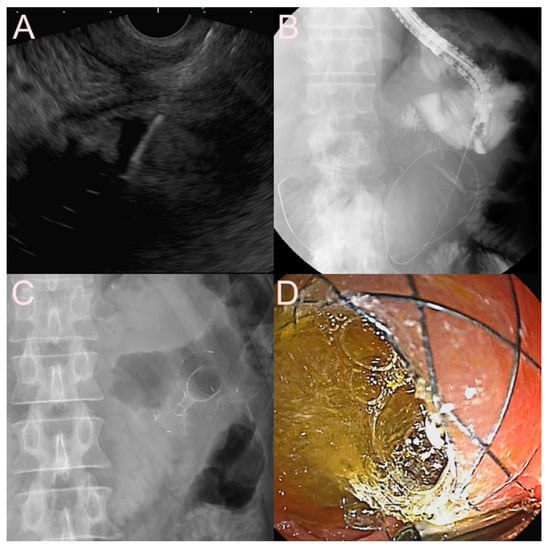

2.5. Stent for EUS-Guided Creation of Entero-Enteric Anastomosis